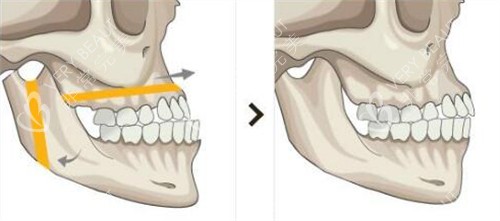

何医生团队用三维CT和咬合模型分析我的骨骼问题,明确告诉我:“单纯正畸改善有限,双鄂截骨才能让上下颌骨回归正确位置。”